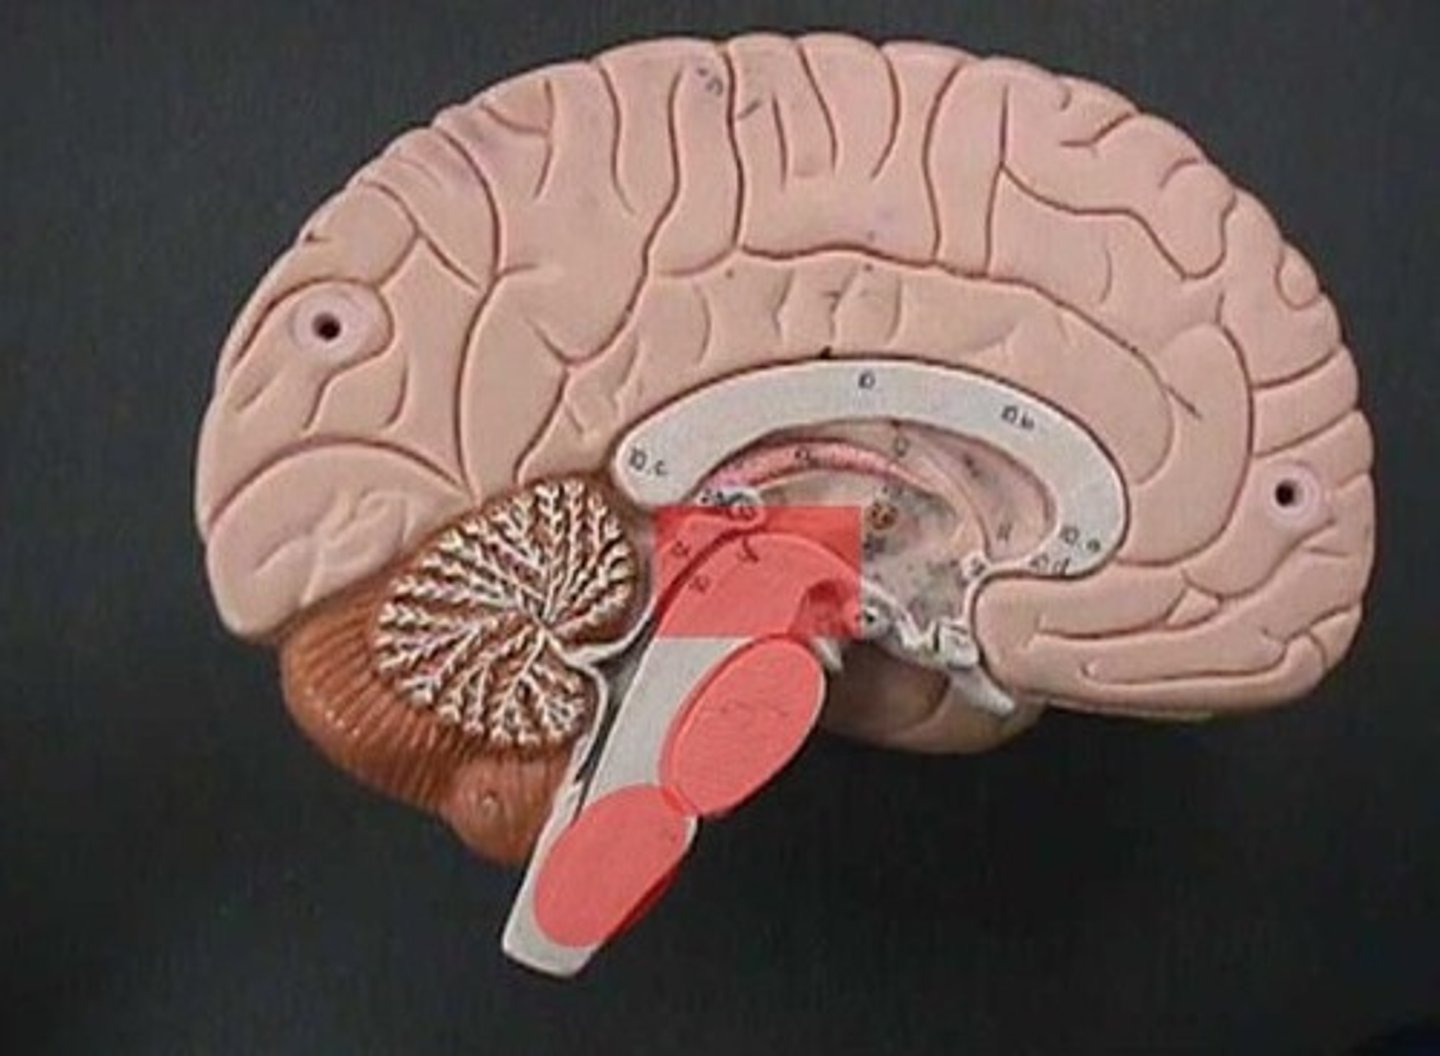

brain stem

midbrain (mesencephalon)

pons

medulla oblongata

pyramids

cerebellum

tentorium cerebelli

between cerebrum and cerebellum